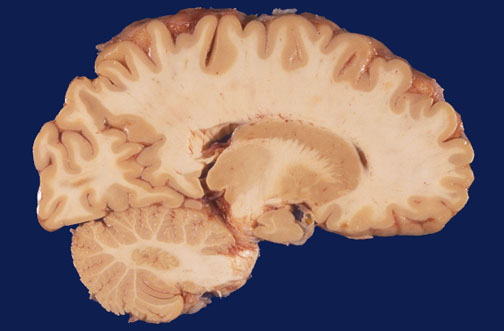

| In this sagittal section lateral to the midline can be seen the Rolandic fissure with the precentral gyrus (motor cortex) and the postcentral gyrus (somesthetic cortex). The frontal lobe, the parietal lobe, and the occipital lobe are well demarcated. The caudate nucleus, the pulvinar of the thalamus, and the lateral geniculate nucleus are seen. The dentate nucleus of the cerebellum is prominent. |